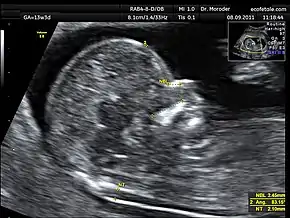

![]() Measurements of fetal nuchal translucency, nasal bone and facial angle according to the standards of the Fetal Medicine Foundation | |

Nuchal scan (NT procedure) is performed between 11 and 14 weeks of gestation, because the accuracy is best in this period. The scan is obtained with the fetus in sagittal section and a neutral position of the fetal head (neither hyperflexed nor extended, either of which can influence the nuchal translucency thickness). The fetal image is enlarged to fill 75% of the screen, and the maximum thickness is measured, from leading edge to leading edge. It is important to distinguish the nuchal lucency from the underlying amniotic membrane.[8]